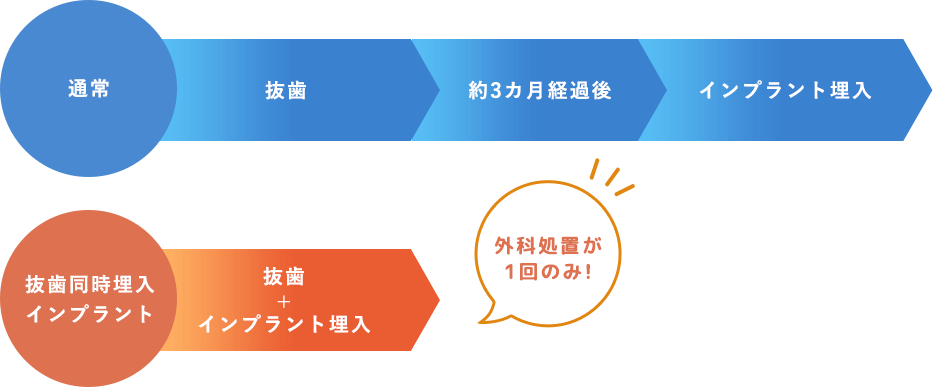

抜歯同時埋入インプラント

(即時荷重インプラント)に対応

歯を抜くと同時にインプラントを埋入する治療法です。

一般的なインプラント治療は、手術から仮歯を入れるまで3~6カ月の安静期間が必要でしたが、即時荷重インプラントであれば当日中に仮歯を装着することができます。

- 通院回数が減り、患者様の負担が軽減

- 歯のない期間がなく審美面でも優れている